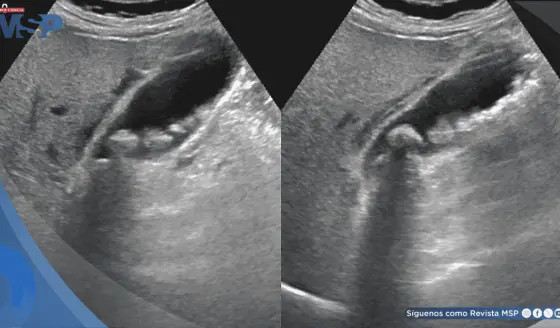

La perforación septal permitió el drenaje parcial pero insuficiente del contenido menstrual. Esta clasificación tiene implicaciones terapéuticas directas, siendo la resección quirúrgica completa del tabique obstructivo (marsupialización) el tratamiento definitivo.